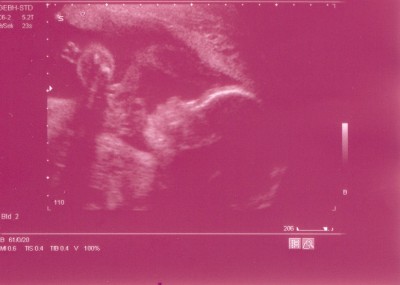

Hier mal ein neues US-Bild (Sie spielt da gerade mit der Nabelschnur)